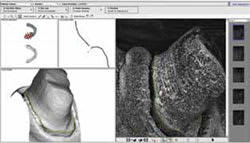

Figure 9 Case 1 design. | Figure 10 Case 2 scan anomaly. | ||||||

Full-contour wax crown designs were created starting with a default library tooth. Design adjustments were made with advanced shaping tools within the 3Shape software (Figure 9). 3Shape's Dental Designer software allows for multiple restorations, including multiple single units as well as bridges, on the same arch, to be designed simultaneously. This is a case that would have been extremely difficult to design using 3M ESPE's Lava Design software, which only allows for single unit or bridge designs.

A scan anomaly was found on the distal wall of tooth No. 12, and software tools within the 3Shape design software were used to remove the anomaly (Figure 10). The three-unit bridge framework was designed using simple copings, a pontic, and connectors. Proper support of porcelain was ensured by using the software shaping tools to extend the marginal ridge and cusp areas (Figure 11).